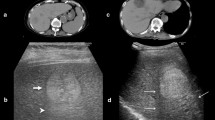

Twenty-three studies including 4947 patients were included. The risk of bias was mainly related to analysis domain. The RQS reached an average of (37.7 ± 11.4)% with main methodological insufficiencies of scientific study design, external validation, and open science. The pooled areas under the receiver operating curve (AUC) were 0.85 (95% CI 0.82–0.89), 0.87 (95% CI 0.83–0.92), and 0.74 (95% CI 0.67–0.80), respectively, for CT, MR, and ultrasound radiomics models. The pooled AUC of ultrasound radiomics model was significantly lower than that of CT (p = 0.002) and MR (p < 0.001). Portal venous phase for CT and hepatobiliary phase for MR were superior to other imaging sequences for radiomic MVI prediction. Segmentation of both tumor and peritumor regions showed better performance than tumor region.